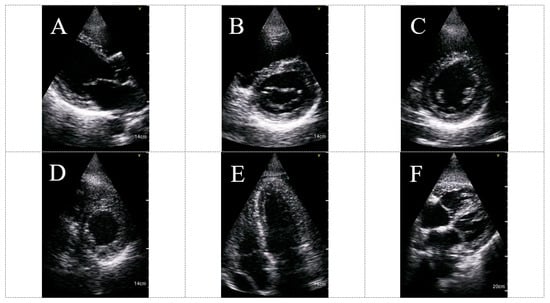

Abnormal echocardiogram independently predicted the composite endpoint (OR 6.19; 95% CI 1.50–25.57, p= 0.012). Another important finding was that among low-risk patients (room-air oxygen saturation ≥ 94%), the prevalence of the composite endpoint was very low (3.1%) with a low positive predictive value for HUD use in this group of patients. These results indicate that the utilization of a HUD is an important “rule-out” tool among COVID-19 high-risk patients and should be integrated early into their routine evaluation. HUD can be utilized for different echocardiographic clinical applications in the setting of COVID-19 infection. Figure 4 shows examples of routine HUD-acquired echocardiographic images in COVID-19 patients.

Figure 4.

HUD acquired echocardiographic images in COVID-19 patients: parasternal long axis view (A), parasternal short axis view (MV level) (B), parasternal short axis view (PM level) (C), parasternal short axis view (apex level) (D), apical four chambers view (E) and subcostal view (F). The imaged were acquired using the Vscan Extend with the Dual Probe, General Electric. Abbreviations: HUD, hand-held ultrasound device; MV, mitral valve; PM, papillary muscles.